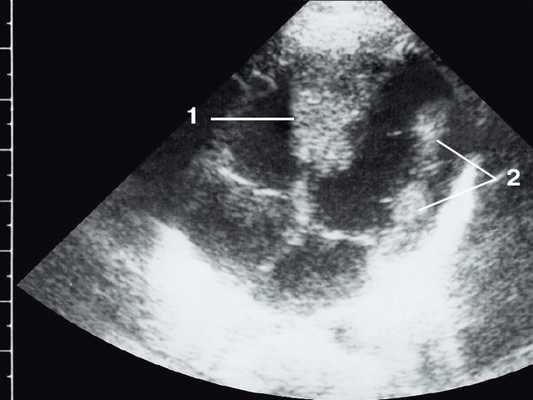

Широкое внедрение в практику ультразвуковой диагностики позволило перейти от аутопсийной статистики к прижизненному выявлению. Эхокардиография - первый метод выявления рабдомиомы сердца и контроля состояния пациента в динамике. Учитывая очень большое число семейных случаев, необходимо обследование всех ближайших родственников, особенно при наличии у них пятен цвета кофе с молоком, депигментированных по типу шагреневой кожи, параунгвальных и параореолярных фибром, ранних миом матки, инфантильных спазмов, судорожных припадков и других признаков факоматозов. При семейных обследованиях рабдомиомы сердца могут выявляться у совершенно бессимптомных носителей (рис. 1, 2).

Рис. 1. Эхокардиограмма ребенка (девочки) с рабдомиомой. Крупный узел рабдомиомы в межжелудочковой перегородке (1) и менее крупные узлы в задней стенке левого желудочка (2). Эхоплотность образований выше, чем миокарда.

Рабдомиома сердца эхографически выглядят как достаточно четко очерченные образования. Чаще всего располагаются в миокарде левого желудочка, реже - в правом, еще реже - в предсердиях, кавоатриальных и атриовентрикулярных соединениях, эпикарде. Метастазирование не типично [8]. Наличие двух и более рабдомиом четко коррелирует с туберозным склерозом, одиночные рабдомиомы сердца такой связи, как правило, не имеют. По нашему опыту (18 пациентов), чем меньше объем новообразования, тем выше акустическая плотность, приближающаяся к эталонной эхоплотности (эндо-, эпи- и перикард). Эхоплотность больших рабдомиом практически не отличается от эхоплотности миокарда. В толще новообразования выявляются мелкие эхонегативные очажки (области некрозов) и эхопозитивные очажки (отложения кальция) (рис. 3).